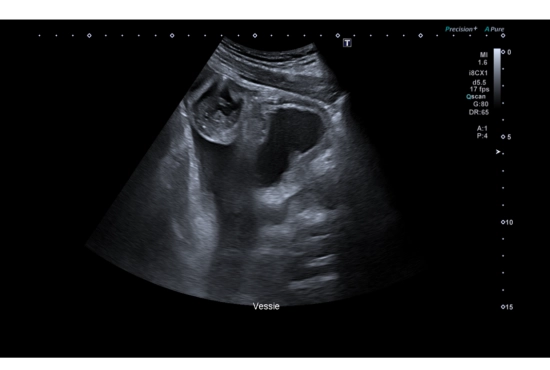

"Quand une douleur testiculaire cache une hernie inguinale : l'importance de l'exploration systématique des orifices herniaires"

25/04/2026

Lire la suite